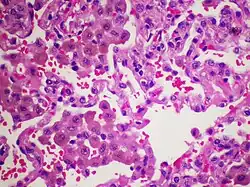

Złuszczające śródmiąższowe zapalenie płuc (ang. desquamative interstitial pneumonia, DIP) – rzadka choroba zaliczana do idiopatycznych śródmiąższowych zapaleń płuc występująca u osób palących[1], najczęściej w wieku 30-50 lat. Choroba objawia się kaszlem i dusznością, w badaniu przedmiotowym stwierdza się palce pałeczkowate, podczas osłuchiwania stetoskopem trzeszczenia nad dolnymi polami płucnymi. W gazometrii wykazać można hipoksemię. W badaniu rentgenowskim klatki piersiowej stwierdza się zmiany o charakterze "mlecznego szkła" (nieznaczne zacienienie obszaru płuc z widocznym rysunkiem naczyń krwionośnych[2]). W badaniu tomokomputerowym widoczne są zmiany o charakterze "mlecznego szkła" i siateczkowate zlokalizowane na obwodzie płuc. W diagnostyce wykorzystuje się również badanie histopatologiczne tkanki pobranej w czasie biopsji płuca. W leczeniu stosuje się kortykosterydy. Opisano skuteczną terapię metyloprednizolonem u 10-letniego dziecka[3].